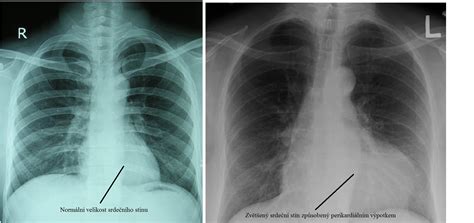

Príčina šelestu u mačiek obyčajne nemôže byť odhalená len auskultačným vyšetrením/posluchom. Mnoho benígnych šelestov môže znieť rovnako ako šelesty pri vážnych ochoreniach srdca. Tak ako pri mačkách aj pri psoch sa môže váš veterinárny lekár rozhodnúť spraviť rentgenový snímok hrudníka, echokardiografiu srdca, EKG, 24 hodinový Holter monitoring, alebo sa rozhodne poslať vás na tieto vyšetrenia ku odbornému lekárovi - kardiológovi.